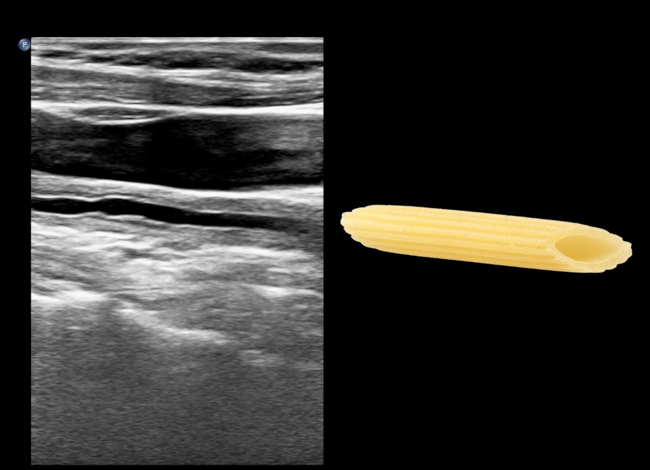

El signo del macarrón fue descrito por primera vez por Hiroaki Maeda en 1991. En su estudio de 23 pacientes con diagnóstico de arteritis de Takayasu (AT), demostró el engrosamiento difuso del complejo mio-intimal con ecografía modo-B en 19 pacientes.1 El engrosamiento parietal homogéneo de la carótida (►Fig. 1 y ►Fig. 2) se asemeja a un tipo de pasta, el macarrón, de característica forma tubular (►Fig. 3).